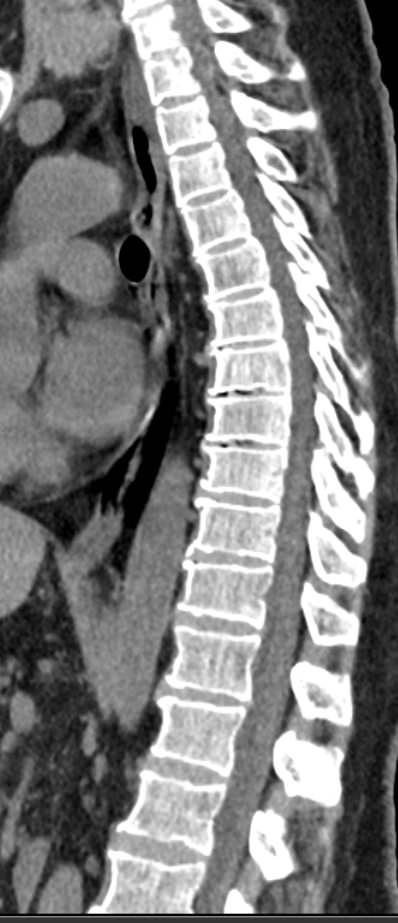

Мультиспиральная компьютерная томография (МСКТ) является современным, высокоинформативным методом диагностики различной патологии позвоночного столба. Благодаря МСКТ можно визуализировать костную структуру позвонков, выявить воспалительные, дегенеративные и опухолевые процессы на исследуемом уровне. В основе метода лежит использование ионизирующего излучения и способность различных тканей по-разному поглощать рентгеновские лучи.

В нашей клинике КТ двух отделов позвоночника проводится на новейших мультиспиральных томографах экспертного уровня TOSHIBA AQUILION (64-срезовый и 128-срезовый). Сканеры производят тончайшие срезы исследуемой зоны толщиной от 0,5 мм и позволяют визуализировать костные структуры позвоночника с высокой детализацией. Увеличенное количество высокочувствительных детекторов аппаратов обеспечивает высокую разрешающую способность и четкость изображений, при этом позволяет выполнить исследование в течение нескольких секунд с минимальной дозой облучения.

Инновационные возможности мультиспиральных томографов, которыми оснащены наши медицинские центры, позволяют создавать 3D-модели позвоночника на рассматриваемом уровне для более точной локализации очага и оценки взаимного расположения органов и тканей.